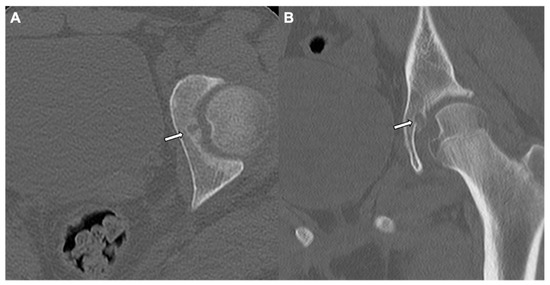

4. Enostosis (Bone Island)

| Lesion Location | Paranasal sinuses, mainly frontal and ethmoidal | Axial skeleton (spine, pelvis, and ribs); long bones | Long bones, mainly femur | Spine and long bones |

| Radiographic/CT features | Juxtacortical, well-circumscribed homogenous sclerotic lesion | Homogenous intra-medullary sclerotic focus with spiculated margins | Small (less than 2 cm) cortical lucency with extensive surrounding sclerosis | Expansile large (more than 2 cm) lucent lesion with matrix mineralization |